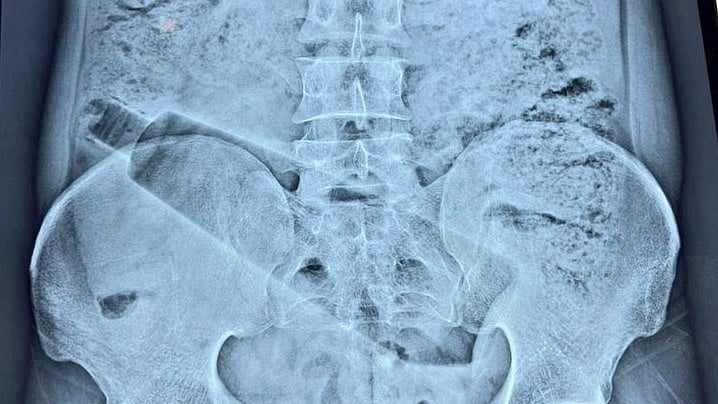

The 38-year-old man, a resident of Saket Colony, had reportedly been suffering from severe abdominal pain for nearly 36 hours before being taken to a private hospital. Initial examination and an X-ray revealed that a one-litre plastic bottle was stuck inside his body.

According to senior surgeon Dr Sunil Sharma, the case was highly sensitive due to the risk of injury to the intestines and rectum during the procedure. A team of doctors carried out a carefully planned surgery, which lasted around one hour and ten minutes, to safely extract the object.